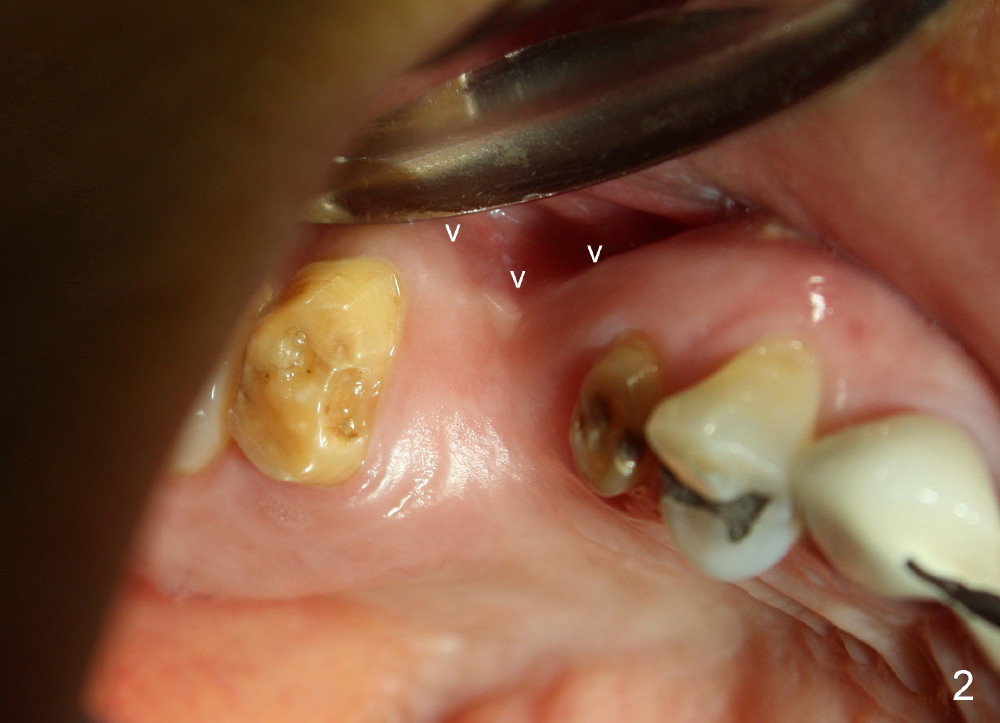

The bone density (Fig.1 white *) at the edentulous area (#3) is lower than that at the dentulous one (black *, 50 year-old man). The buccal plate is also atrophic and concave (Fig.2,3 arrowheads). A series of bone expanders are used to form osteotomy (following 1.6 mm pilot drill) at the depth of 14 mm (Fig.3 E 3.0 mm in diameter). When the last expander (4.3 mm) is removed from the osteotomy, the buccal plate appears to have been moved buccally (Fig.5 arrowheads). A 5.3x14 mm submerged implant (Fig.6 I) is placed with insertion torque >35 Ncm. The buccal plate seems to improve following placement of an 8.2 mm healing abutment and suturing (Fig.7). No bone graft is used. The buccal plate remains normal 12 days postop (Fig.8). It is slightly concave 3 months postop (Fig.9) with minimal bone resorption at the crest (Fig.10 (H: healing abutment),11 (A: cemented abutment). Nine months post cementation (12 months postop), bone resorption at the crest remains minimal (Fig.12) while the buccal plate (Fig.13 *) at #3 remains strong. Bone loss appears not to get worse 22 months post cementation (Fig.14). Soft and hard tissues remain healthy around the implant crown 3 years (Fig.15) and 3.5 years (Fig.16,17) post cementation.